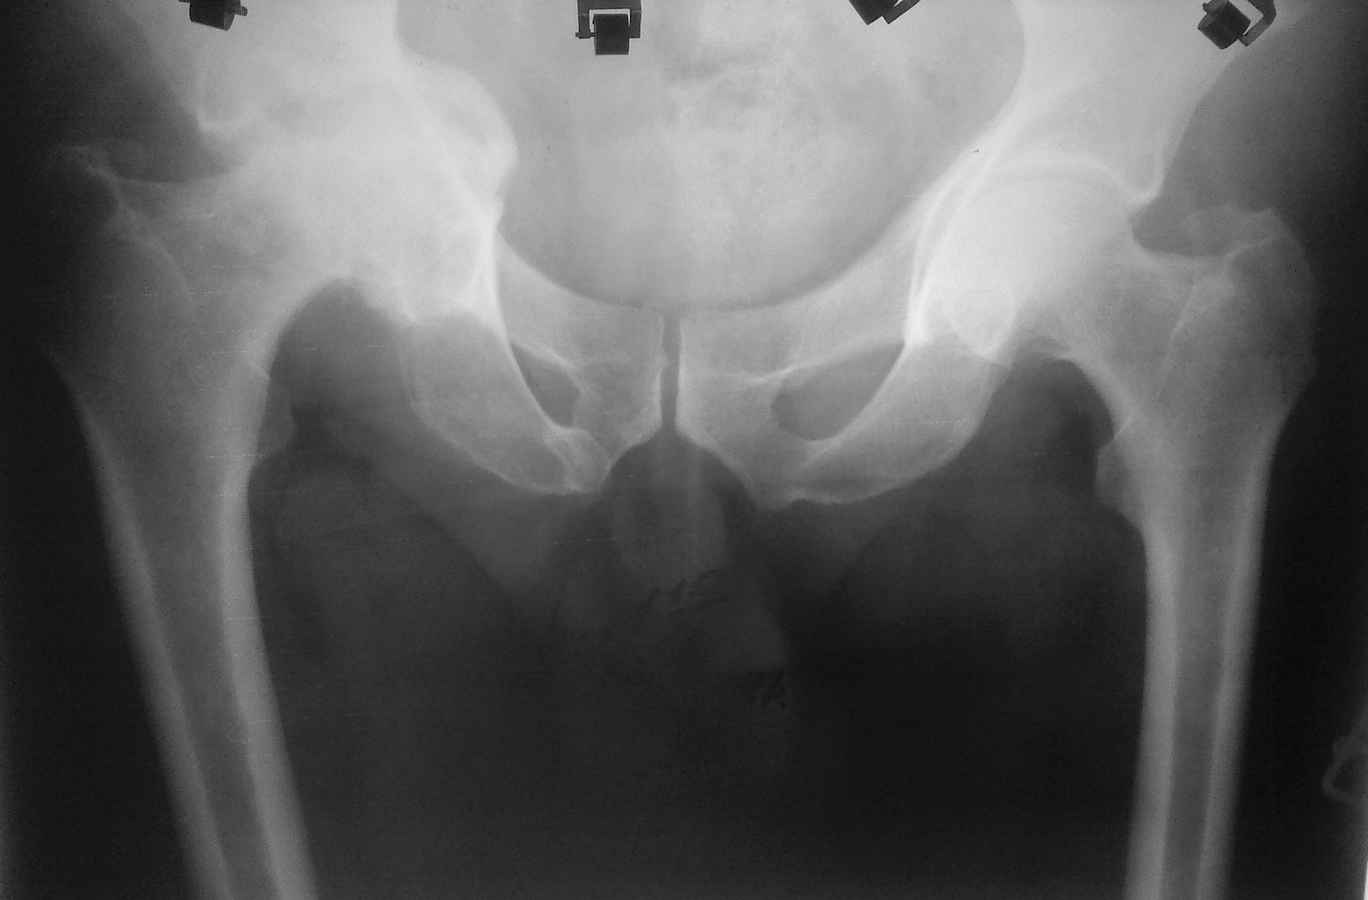

протрузионный коксартроз

Здравствуйте. Уважаемые коллеги, поделитесь опытом у кого какая тактика при протрузионных коксартрозах

У нас в клинике принято выполнять костную пластику дна стружкой из гололки, а потом цементную чашку (снимки прилагаю). Выскажите свои взгляды на эту проблему, пожалуйста.